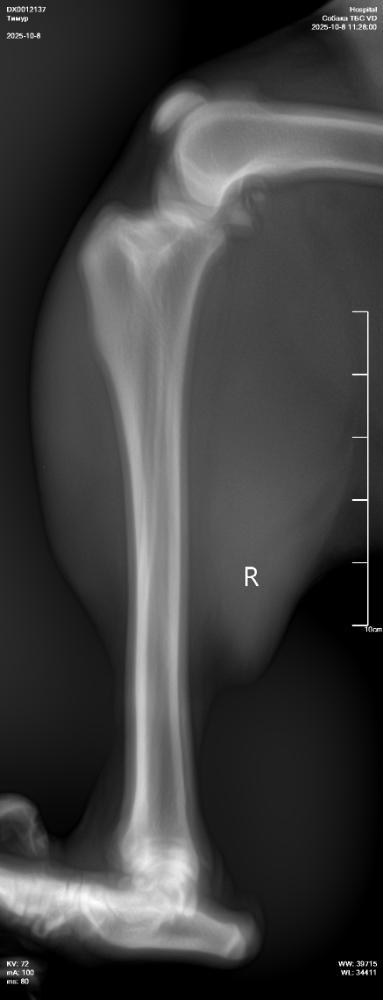

NataP Опубликовано 8 октября, 2025 Опубликовано 8 октября, 2025 Здравствуйте. Три дня назад после прогулки Тимур захромал, хотя сильных нагрузок не даём, немного поиграли с пуллером. Сегодня създили в клинику, сделали снимки без седации, кое как смогли завалить, сопротивлялся, поэтому снимки получились не такие, как хотелось бы. Но даже по ним нам ставят дисплазию и рекомендуют операцию по протезированию. Хочу проконсультироваться онлайн в Москве. Посоветуйте, пожалуйста, где сейчас лучше консультироваться, и подойдут ли такие снимки, или лучше переделать под седацией. Сейчас пока выписали онсиор или робексеру на 10 дней, но Омез сказали, давать не нужно, а я сомневаюсь, может всё-таки давать? Простите за много букв, просто в панике пока, а кроме вас не к кому обратиться. Снимки прикрепила.

Кирюша и Маруся Опубликовано 9 октября, 2025 Опубликовано 9 октября, 2025 Снимки без седации полная дезинформация. А к врачам, которые делают их для постановки диагноза лучше не ходить. Сделайте нормальные снимки с седацией у профи. При сомнении и пон азначению врача - МРТ. А обезбол крупной моложой собаке на травированную связку - это странно, так как нужно граничивать движение, а не просто снимать болевой и давать скакать. По врачам в МСК: Мезин, Еремин, Ягников, Воронцов, Самошкин, Середа, Давыдов, Гранин... Выбирайте любого. Нормальные рентгены делают они все. 1

NataP Опубликовано 9 октября, 2025 Автор Опубликовано 9 октября, 2025 То есть эти снимки вообще безполезны? Зря только с Тимуром воевали, чтоб на стол уложить(

Звезда Севера Опубликовано 9 октября, 2025 Опубликовано 9 октября, 2025 К сожалению, да. Такие снимки не информативны. Я так понимаю, что вам ближе в Нижний Новгород ехать? Может, там найти хороших специалистов?